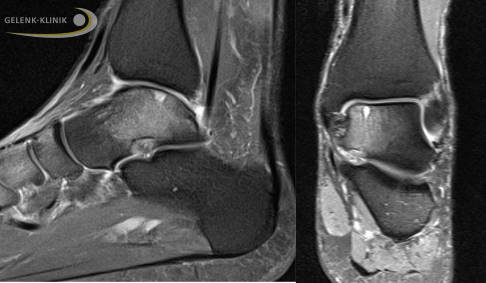

Die Kernspintomographie (MRT) ist wenig geeignet, um einen Knorpelschaden am Sprungbein direkt darzustellen. Dafür zeigt das MRT gegebenenfalls ein Knochenödem oder Knochenzysten als Zeichen der Knochenreaktion.

Stellt der Arzt eine Veränderung der Knochenstruktur fest, muss er immer entscheiden, ob diese Schädigung durch einen Knorpelschaden entstanden ist oder ob der Knochen ohne eine Schädigung des Knorpels erkrankt ist wie bei der Osteochondrosis dissecans.

Hier sind verschiedene Ansätze in der Diagnostik sinnvoll. Der direkte Nachweis einer Schädigung der abdichtenden und dämpfenden Knorpelschicht kann nur im Rahmen einer invasiven Arthrografie erfolgen.

Hierbei wird die Gelenkschmiere mit einem jodhaltigen Kontrastmittel versetzt. Um die Verteilung der Gelenkschmiere genau darzustellen, benötigt man eine Darstellung mit Röntgenstrahlen ähnlich einer Computertomographie oder einer digitalen Volumentomographie (DVT). Letztere kann unter Belastung durchgeführt werden, womit sich zeitgleich eine Stellungsbeurteilung durchführen lässt.